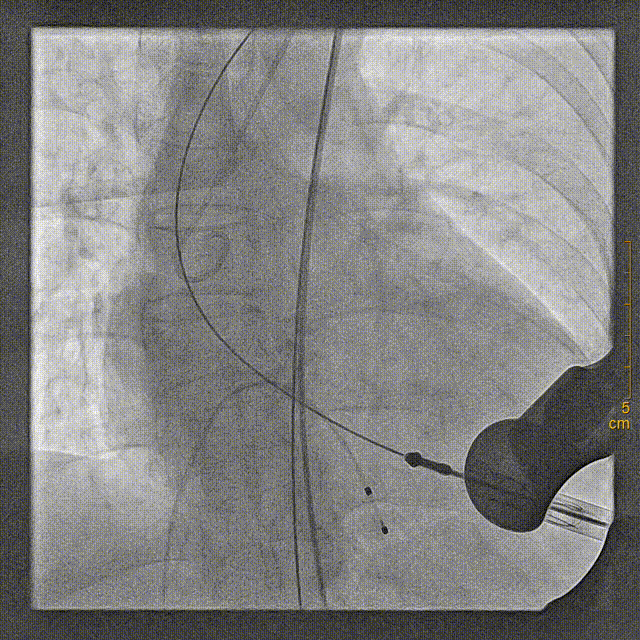

将装置好J-Valve23mm主动脉瓣的输送鞘送至主动脉瓣瓣环平面,释放定位装置并造影定位

稳定释放瓣膜